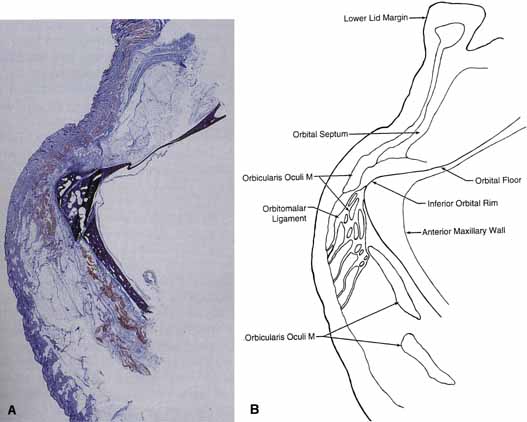

Lockwood20 described a hammock-like structure extending from the lateral orbital

tubercle to the medial canthal tendon comprised of the fused fascia

of the inferior rectus and inferior oblique muscles. The retractor

complex of the lower eyelid is composed of aponeurotic expansions of

the inferior rectus. These expansions form the capsulopalpebral head, which

divides to extend anteriorly around the inferior oblique muscle

and then fuses into Lockwood's ligament in front of the inferior

oblique to form the capsulopalpebral fascia.21 This fascia connects Lockwood's ligament to the inferior fornix, to

the inferior border of the tarsus, and to the preseptal orbicularis

muscle and skin at the level of the lid crease (see Fig. 12). It also contains the adrenergic smooth muscle fibers of the inferior

tarsal muscle, which are more diffusely distributed than in Müller's

muscle and do not insert directly onto the tarsus. Lockwood's

suspensory ligament is strongest immediately anterior to the

inferior oblique muscle and may help support the globe after removal

of the orbital floor. However, globe ptosis can occur after orbital

decompression for thyroid eye disease.  Fig. 12 Normal lower lid anatomy in cross section. (CPF, capsulopalpebral fascia; CPH, capsulopalpebral head; IOM, inferior oblique muscle; IRM, inferior rectus muscle; LL, Lockwood's ligament; MF, malar fat; OF, orbital fat; OM, orbicularis muscle; OML, orbitomalar ligament; OS, orbital septum; T, tarsus) Fig. 12 Normal lower lid anatomy in cross section. (CPF, capsulopalpebral fascia; CPH, capsulopalpebral head; IOM, inferior oblique muscle; IRM, inferior rectus muscle; LL, Lockwood's ligament; MF, malar fat; OF, orbital fat; OM, orbicularis muscle; OML, orbitomalar ligament; OS, orbital septum; T, tarsus)